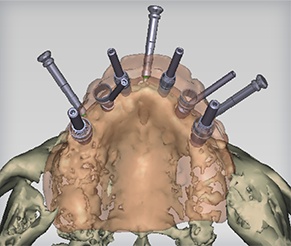

Computer-Guided Surgery

Computer-guided surgery, with the aid of modern and increasingly sophisticated software, enables the surgeon to plan the operation by means of a computer program, step by step, starting from a proper dental CT scan. It also allows very accurate transformation of this virtual surgery to a non-traumatic and micro-invasive real surgery.

After the 3-D CT scan of the dental area to be treated is completed, this scan will be imported into a highly technological software program that will elaborate two- and three-dimensional anatomical structures, enabling us to carry out a virtual computer simulation. We plan the implant placement and prosthetic structure precisely to a tenth of a millimeter. Other additional advantages of this method are the possibility of preventing surgical risk, the speed of this operation, and the rehabilitation period of the patient without the impact characteristics of traditional techniques.